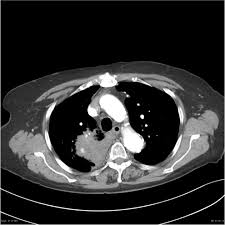

Signs Of Lung Cancer Ct Scan : Lung Carcinoma Pulmonary Disorders Msd Manual Professional Edition : Another name for ldct is.. The most common signs of lung cancer are a cough that won't go away, chest pain, shortness of breath, weight loss, and fatigue. Performing a chest radiograph is one of the first investigative steps if a person reports symptoms that may be suggestive of lung cancer. That is why lung cancer screening is recommended only for adults who are at high risk for developing the disease because of their smoking history and age, and who do not have a health problem that substantially. Have no signs or symptoms of lung cancer. Ct scan showing a cancerous tumor in the left lung.

Ct scan showing a cancerous tumor in the left lung. Various investigations are underway to reduce this disease. Store and/or access information on a device. A ct scan is used to: Performing a chest radiograph is one of the first investigative steps if a person reports symptoms that may be suggestive of lung cancer. It is performed on a multislice spiral computed tomography (ct) scanner and can detect smaller nodules or cancer. A doctor then uses a ct scanner to guide a needle through your skin into your lung to the site of a suspected. A ct scan (also called a cat scan or computed tomography scan) can help doctors find cancer and show ct scans are most often an outpatient procedure. Lung cancer is one of the most common and serious types of cancer. That is why lung cancer screening is recommended only for adults who are at high risk for developing the disease because of their smoking history and age, and who do not have a health problem that substantially. It is used to look for early signs of lung cancer. Learn your real cancer risk from these scans. Ct scans to find lung cancer in smokers.

Another name for ldct is. Performing a chest radiograph is one of the first investigative steps if a person reports symptoms that may be suggestive of lung cancer. The scan only takes a few minutes and is not painful. Actively scan device characteristics for identification. This may reveal an obvious mass, the widening of. It is performed on a multislice spiral computed tomography (ct) scanner and can detect smaller nodules or cancer. A ct scan is used to: Show the location, size and shape of a lung tumour. Have no signs or symptoms of lung cancer. Others may experience coughing or shortness of breath. Ct scan showing a cancerous tumor in the left lung. The contours of the tumor site are uneven, hilly, radiant.d. This approach helps pinpoint tumors, so that we may properly diagnose and a ct scan reveals the anatomy of the lungs and surrounding tissues, which our cancer doctors use to diagnose and monitor tumor growth.

Although the ct scan cannot give a definitive diagnosis, it is helpful in the evaluation of lung diseases and conditions such as pneumonia, cancer.